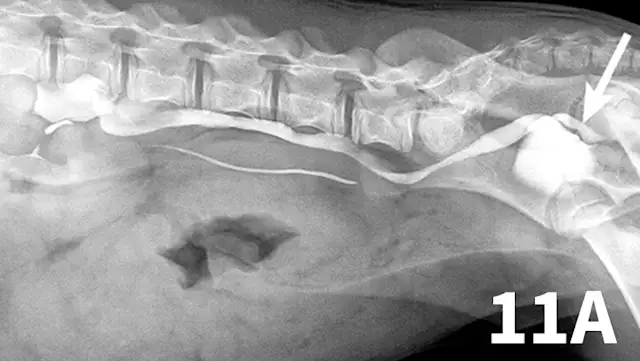

Normal ureters cannot be visualized with survey radiography or ultrasonography, but normal and abnormal ureters are readily visualized with excretory urography. The location of a ureteral obstruction or rupture as well as the presence of an ectopic ureter (especially when combined with pneumocystography) can be documented with excretory urography (Figure 11). A dilated ureter (hydroureter) can be observed with ultrasonography (Figure 12). Pyelocentesis (for cytology and culture) and antegrade pyelography (nephropyelography) (Figure 13) to document obstruction or leakage can be conducted via ultrasound guidance with heavy sedation or anesthesia. Ultrasonography can also be used to visualize retroperitoneal fluid accumulation, which may occur with a ureteral rupture, hemorrhage, or infectious or neoplastic disease. Whereas ureteroliths without hydroureter may be missed on ultrasonography, radiopaque ureteroliths can be observed on survey radiography (Figure 14). Survey radiographic visualization of radiopaque ureteroliths may be facilitated by enemas to empty the colon of fecal material and/or use of a radiolucent paddle to apply regional compression over the ureter to separate adjacent organs (eg, loops of bowel) (Figure 15). Aged cats with chronic kidney disease (CKD) frequently have calcium oxalate nephroliths; in some cases, these nephroliths will migrate into the ureters. Survey radiographs should be employed to rule out ureterolithiasis, especially in cats with acute decompensation of their CKD (Figure 16).

Figure 11A.

Lateral oblique view from a young dog with a left ectopic ureter that was diagnosed with excretory urography. The left ureter and renal pelvis are dilated. The left ureter extends beyond the trigone region of the urinary bladder on the lateral oblique view (arrow).